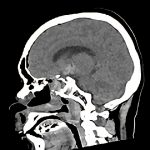

胚細胞腫

断層撮影

手術前1

No.’12_107 手術前1

No.’12_107 手術後